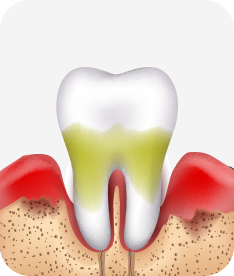

치주염(잇몸병)은 치아에 붙어있는 치석 및 세균 등에 의한 염증반응으로 잇몸뼈가 상실되는 질환을 말합니다.

초기에는 잇몸이 붓거나 잇몸에서 피가 나는 증상이 나타나며 계속 방치하면 치아를 발치해야 할 수도 있습니다.

치주치료는 이러한 치석 및 세균 등을 제거하여 잇몸뼈를 안정된 상태로 유지하는 시술을 말하며, 청담네오플란트에서는 치의학박사 / 전문의가 직접 시술하고 있습니다.

치주염 (중기~말기)

주기적으로 잇몸이 붓고 피가 나며, 욱씬하거나 우리한 통증이 나타남.

치주치료 및 정도에 따라 치주수술(잇몸수술)이 필요함. 향후 관리 정도에 따라 3~6개월 간격으로 내원하여 유지치료를 시행하여야 함.

치주염 (말기)

잇몸이 항상 부어 있으며, 이가

흔들리는 정도가 점점 심해짐.

치주치료가 필요하며, 정도에 따라 치아를 발치하여야 할 수 있음.